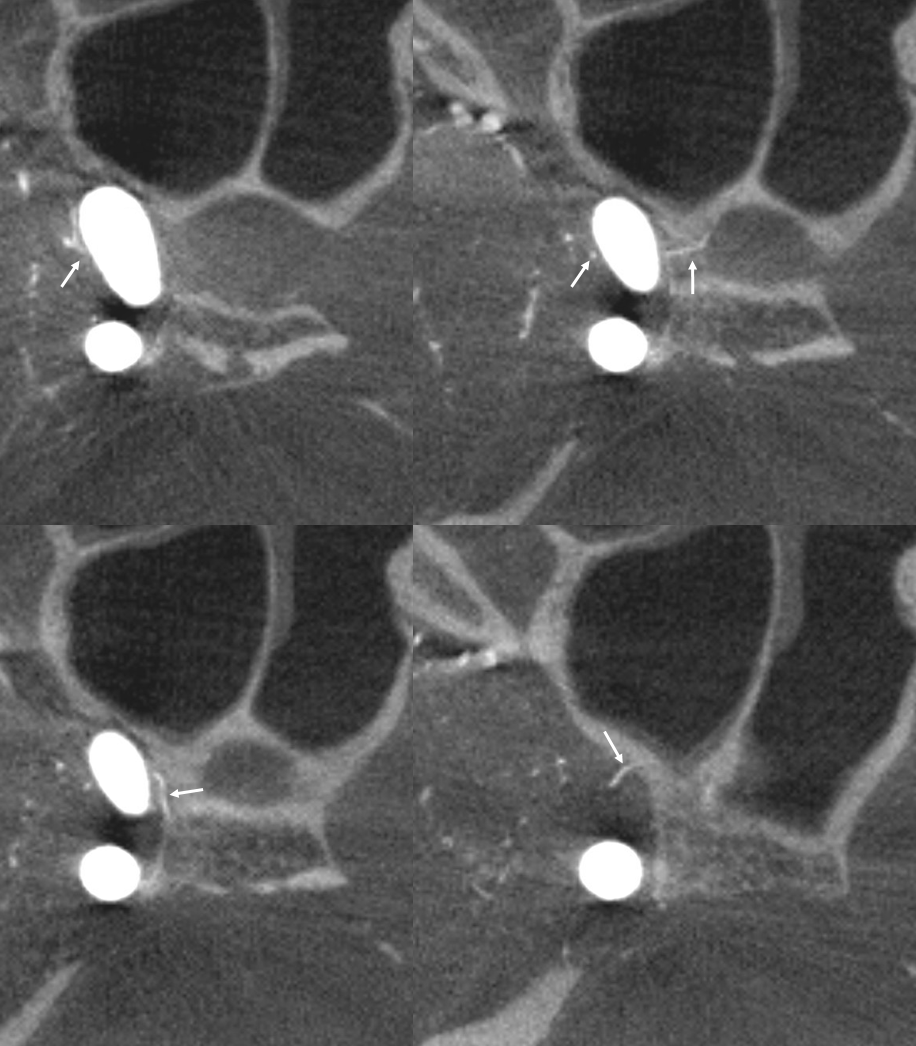

More Optic Nerve Supply — its easier to see on MIPS, but with the right windowing, and stereo, VR imaging is also possible. Here, there are 3 superior hypophyseals seen. The anterior-most (arrow) is usually the largest, suppling the optic nerve (dashed arrow) and chiasm (ball arrow). The middle and posterior hypophyseals (arrowheads) supply the stalk.

Stereo of VR image. Same arrows. The stalk is open arrow.

Another patient — also 3 arteries. Cave origin of the anterior-most (arrows) one. The middle one (arrowheads) also supplies the optic nerve. The posterior one (dashed arrows) is for the stalk.

VR images (stereo pair on bottom). The cave origin of the anterior branch is most beautifully seen in the upper right image.